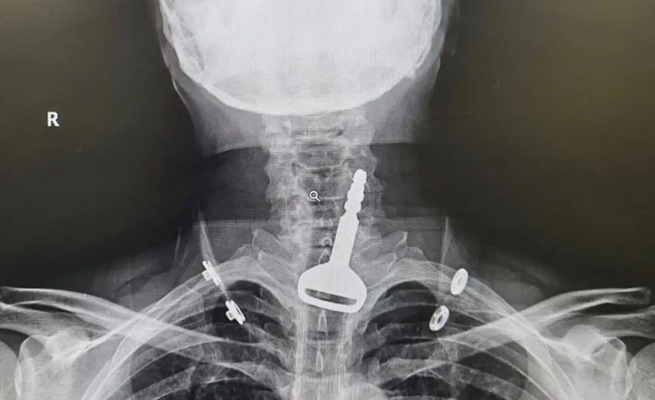

وأوضحت صحة مدينة القنفذة أن المريض، البالغ من العمر 49 عاماً، وصل لقسم الطوارئ وهو يعاني من انسداد بمجرى التنفس، ليتضح بعد الفحص السريري والأشعة وجود مفتاح سيارة عالق في القصبة الهوائية.

واعترف المريض للأطباء المعالجين بأنه ابتلع المفتاح أثناء لهوه به، ما تسبب له في حالة اختناق جزئي تطلب التدخل الجراحي عن طريق المنظار لاستخراج الجسم المعدني العالق.